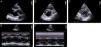

Parasternal long-axis (Figure 1A) and short-axis views (Figure 1B: mitral level, Figure 1C: papillary muscle level) showed a unileaflet mitral valve with an elongated and thickened anterior leaflet, while the posterior leaflet was extremely hypoplastic and almost entirely absent (Video 1). On M-mode imaging of the mitral valve, there was fusion of the anterior mitral E-F and F-A waves, appearing as a single flat E-A wave with loss of the F point (asterisk in Figure 1D) and in contact with the interventricular septum. There were minimal waves (not clearly distinct) of the hypoplastic posterior mitral leaflet and the coaptation zone, depicted by the C point, was posteriorly displaced (Figure 1D). Figure 1E shows the normal M-mode waves of a normal bileaflet mitral valve.

Transthoracic echocardiography. Two-dimensional parasternal long-axis (A) and short-axis [(B) mitral valve level, (C) papillary muscle level] views; M-mode images at the level of the mitral leaflets of the present unileaflet mitral valve case (D) and of a normal bileaflet mitral valve (E). D point: initial diastolic leaflet opening; E point: maximum leaflet opening during the phase of rapid ventricular filling ending at the F point; A point: maximum leaflet opening during atrial contraction; C point: leaflet coaptation point at the beginning of systole. In the present case of a unileaflet mitral valve (D), there is loss of the F point (asterisk) with a flat E-A wave in constant contact with the anterior interventricular septum, corresponding to the opening of the elongated anterior mitral leaflet throughout diastole, while the coaptation point C is posteriorly displaced.